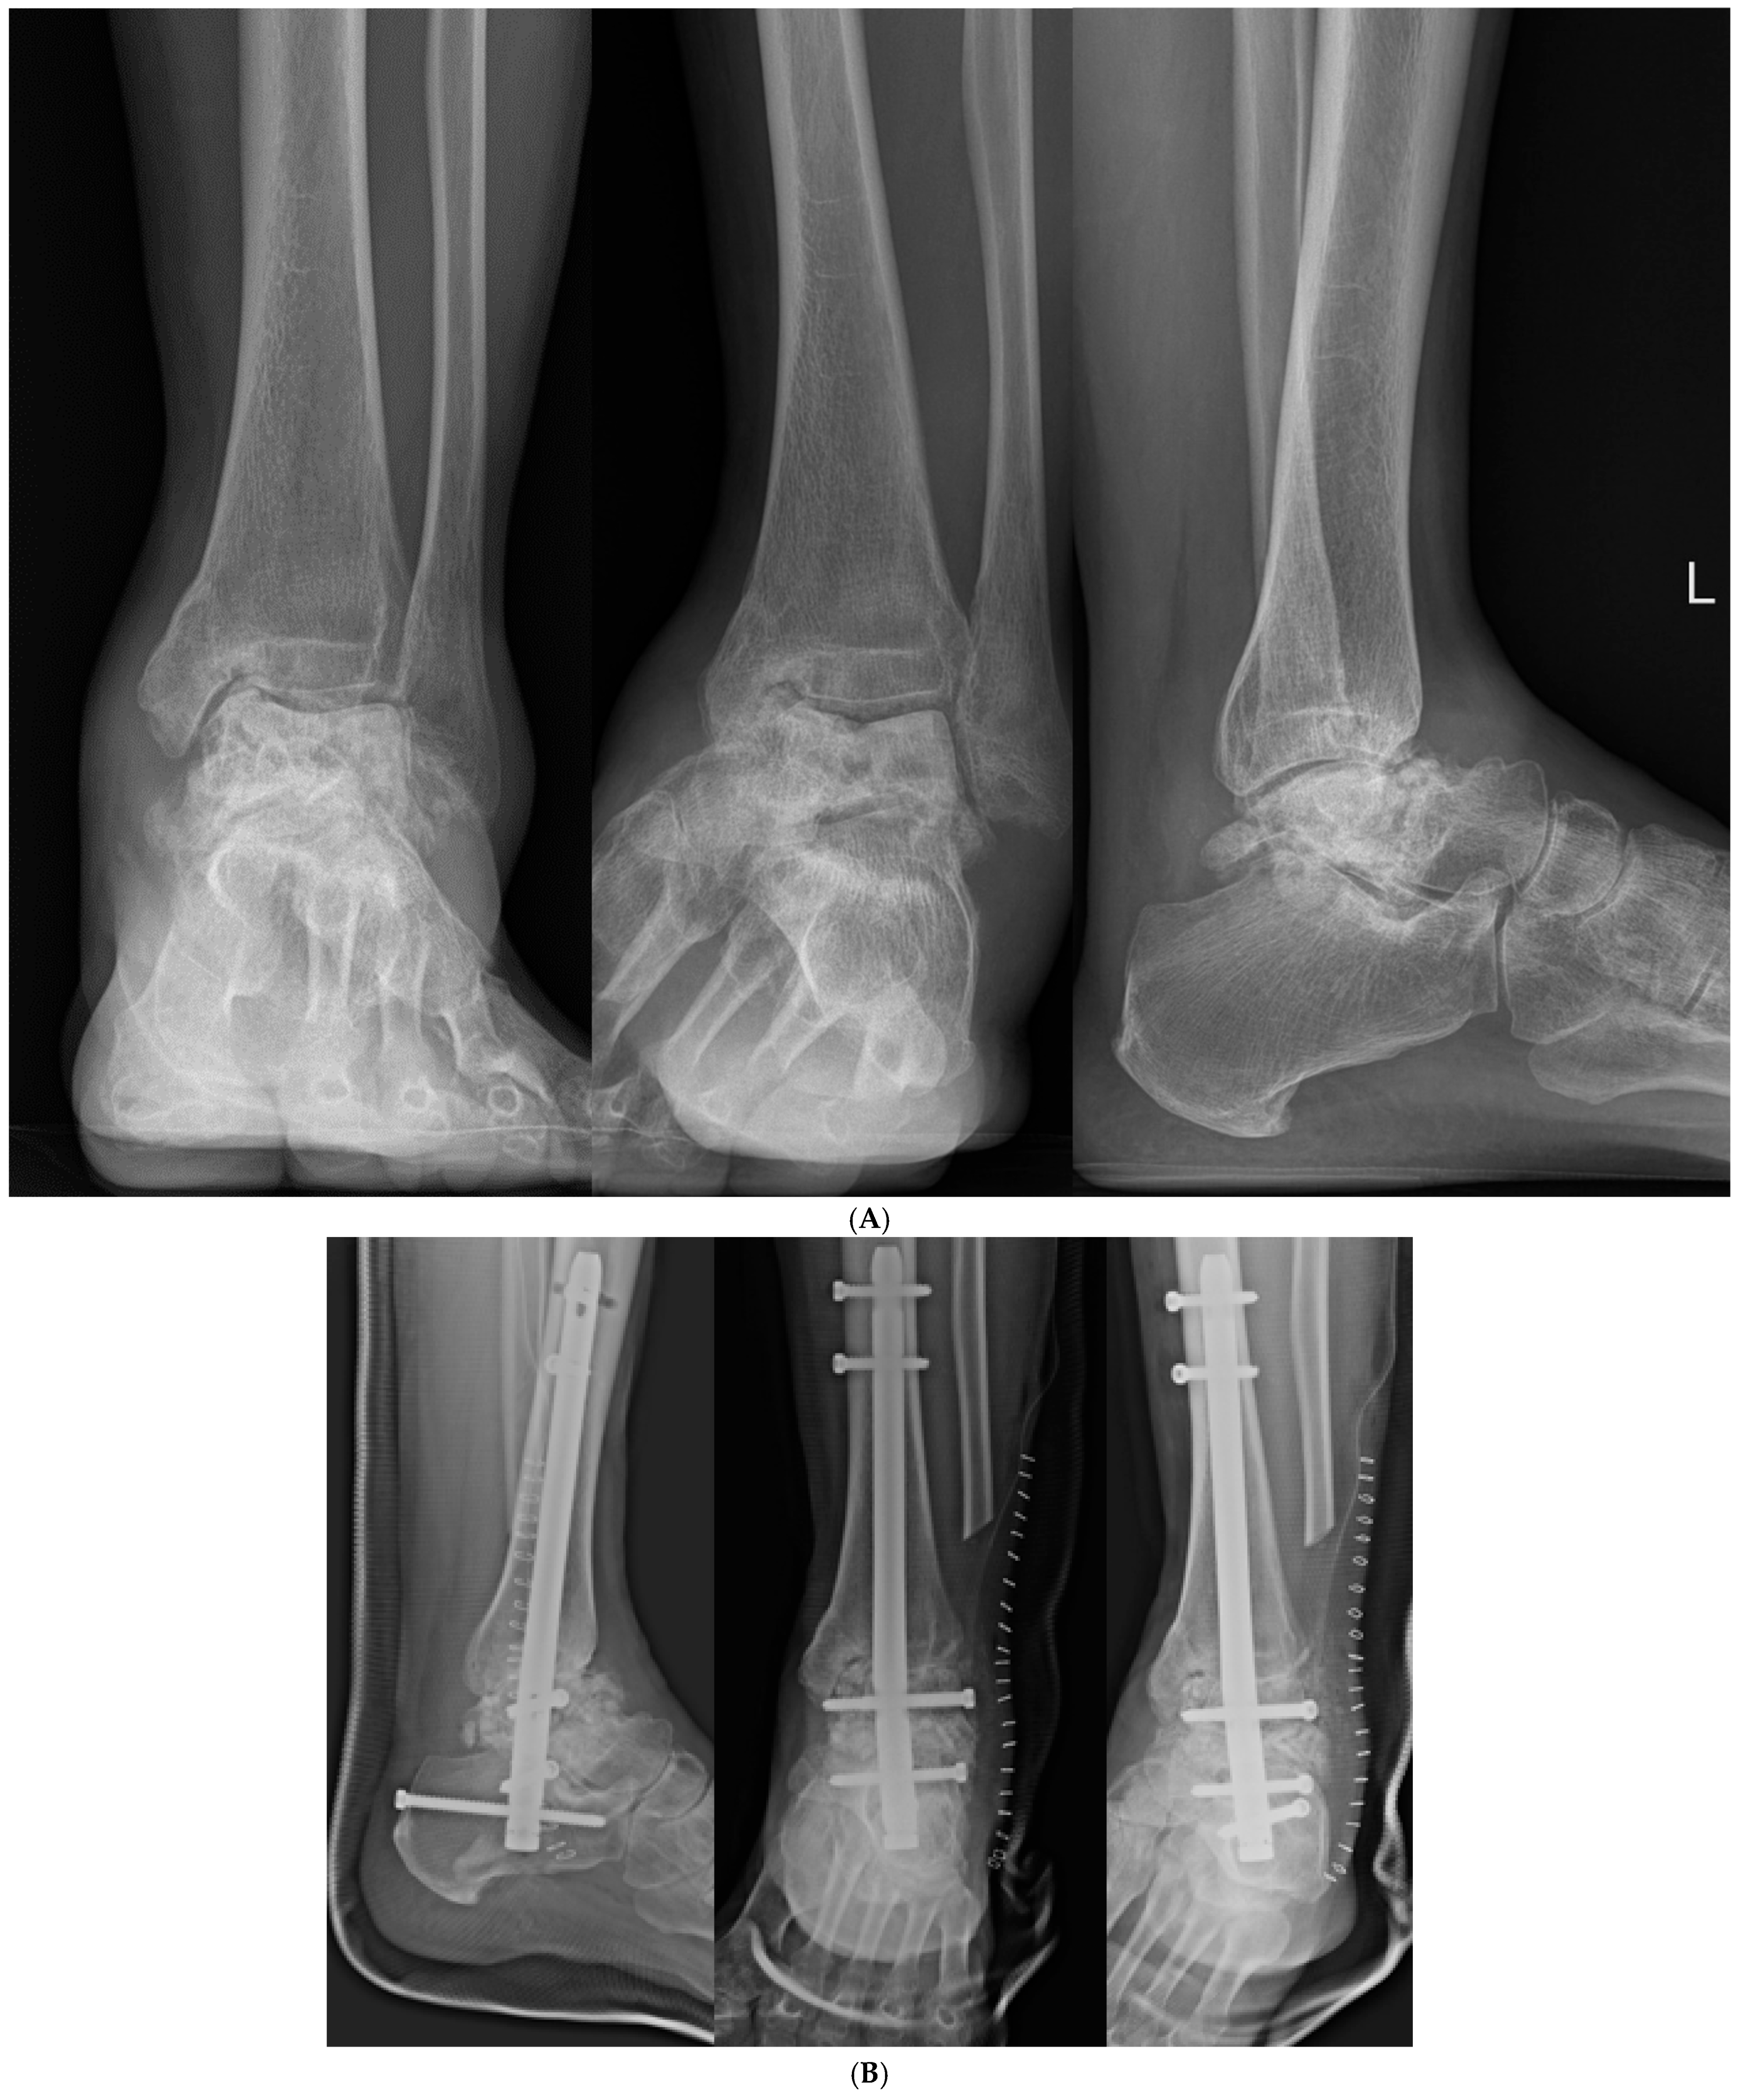

Figure 7. (A) Preoperative and (B) postoperative X-ray Findings.

2.3. Postoperative Care

Postoperatively, patients were immobilized in a non-weight-bearing cast for 4 weeks to ensure initial stabilization and healing. Following this initial immobilization period, patients were transitioned to wearing controlled ankle motion boots for an additional 4 weeks to maintain non-weight-bearing status. After the total 8-week period of non-weight-bearing, patients began progressive, tolerable weight-bearing activities. Full weight-bearing was permitted at 12–16 weeks post-surgery, depending on individual patient progress and radiographic evidence of graft incorporation and arthrodesis (Figure 7 and Figure 8).